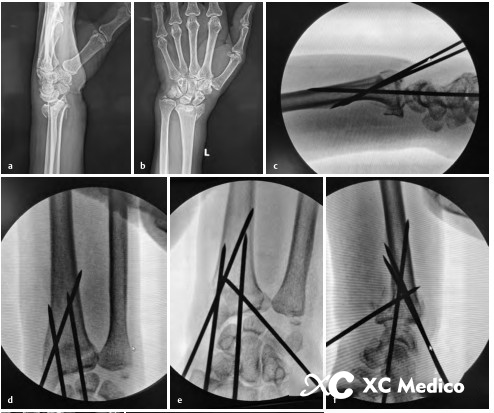

Во -первых, выполняется закрытое восстановление перелома, с медленной и непрерывной тягой, а дорсальное и радиальное смещение корректируется с помощью сгибания пальма и локтевого отклонения. После сокращения рука помещается на свернутый лист, поддерживая пальмовое сгибание и локтевое отклонение (рис. 2а, б) и фиксируется не менее трех чрескожных проводов Киршнера.

Первый K-провод вводится в бугорку Листера, наклонен при 45 ° и направлена на пальмовую кору проксимального фрагмента кости на длинной оси радиуса. Если точка вставки находится на локтевой стороне бугорки Листера, сухожилие Extensor Ollicis может быть повреждено.

Вторая K-провода вставлена 0,5 см дистальна к радиальному стилоидному процессу, K-провода находится под углом 60 ° к радиальной оси и проникает в локтевую кору, проксимальную к перелому.

Третий K-провода фиксируется к фрагменту Lunate Fossa Bone 0,5 см дистально до линии сустава запястья, расположенной между четвертым и пятым компартментами разгибателей. K-провода прикреплена к ладонильной стороне радиуса под углом 45 °, как показано на рисунках A и B ниже.

Классическая чрескожная фиксация проволоки Киршнера расстановки дистального радиуса показана на рисунках AE ниже.